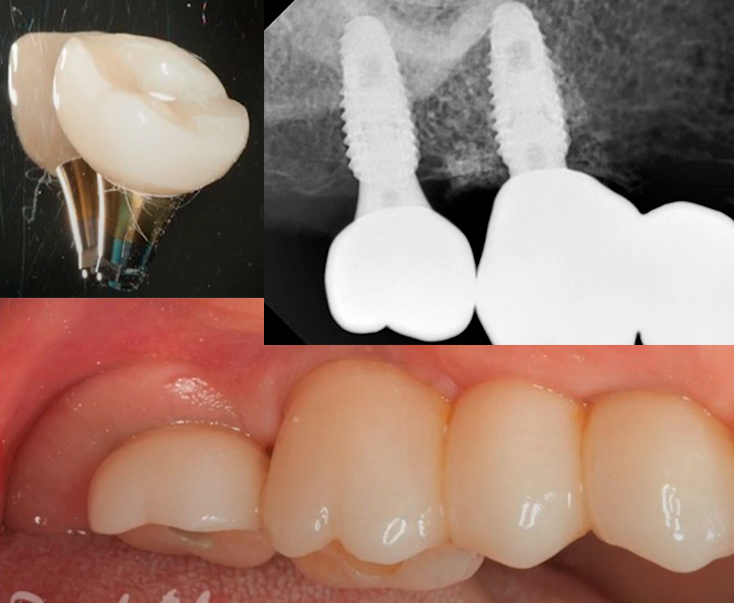

After removing the temporary bridge, a scan body was placed on the final implant. Based on the digital impression, a single zirconia crown was fabricated on a tall titanium base. The single-unit restoration was also torqued to 35 Ncm, which served as the final confirmation of its stability.

The images below show the final three-unit restoration as of September 2020.

Final restoration: bridge and single restoration installed in September 2020. Youtube/ Implantarium/ Rauf Aliyev

The patient returned for a follow-up examination one year later, in September 2021. The gingiva was healthy, with no signs of recession or inflammation.

A photo of the restoration one year after the final version was installed – a bridge + single crown: the soft tissues are healthy. YouTube/ Implantarium/ Rauf Aliyev

The follow-up radiograph also showed that everything was all right. The bone tissue around the implants was even in better condition after a year.

Control radiograph 12 months after restoring the previously mobile implant. YouTube/ Implantarium/ Rauf Aliyev